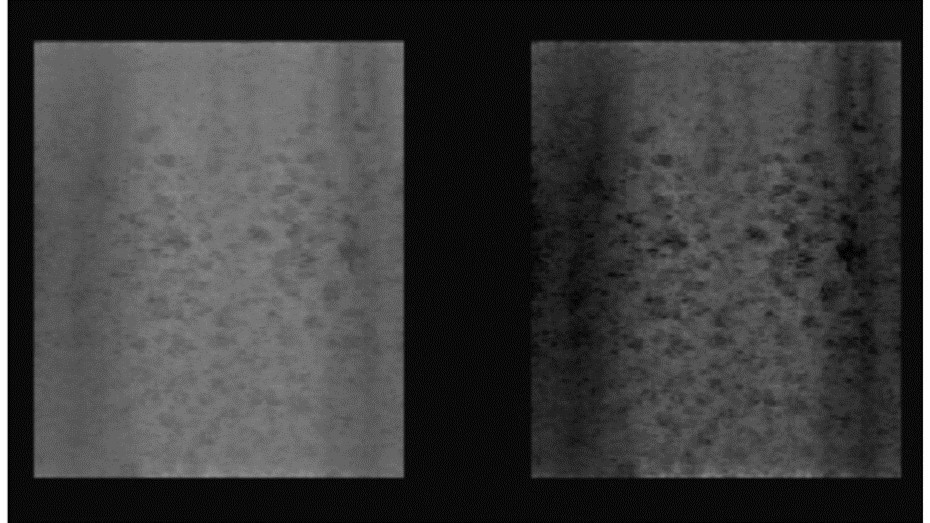

Probes with high acoustic contrast (32.63 dB to 36.66 dB) generated high quality images, Figure 3. Those with acoustic contrast values from 20 dB to 25 dB produced images of lower quality, Figure 4. A typical image produced by a damaged transducer measured as having an acoustic contrast of only 14.68 dB is shown below, Figure 5.

Figure 5.Random Void Phantom) - damaged transducer with inadequate contrast resolution (14.68 dB, Alloca SSD P52105). Original 3D rendered image (left), with increased image contrast (right). Small voids within the RVP with weak contrast cannot be visualised.